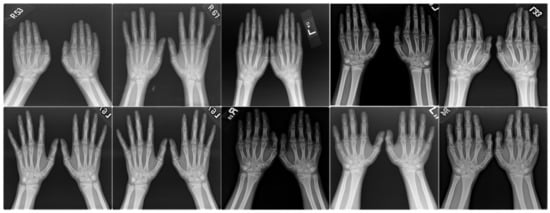

For the validated proposed MCPN-based cryptography mechanism, in experimental tests, the digital images were collected from headshots of 100 children (facial expression image database [36]) and 10 medical images (hand X-ray images, self-created), as seen in Figure 3 and Figure 4, respectively. Each digital image in joint photographic experts group (JPEG) format was digitized to a resolution of 96 × 96 dots per inch and 24 bits per pixel, with each image sized 227 × 227 pixels (N = 227, M = 227, and Nc = 51,529 represents KS), where the row numbers were x = 1, 2, 3, …, 227, and the column numbers were y = 1, 2, 3, …, 227. The proposed MCPN-based cryptography mechanism was designed on a tablet PC (Intel® Xeon®, CPU E5-2620, v4, 2.1 GHz and 64 GB of RAM) using MATLAB 9.0 version software (MathWorks, Natick, MA, USA), with a graphics processing unit (GPU: NVIDIA Quadro P620, 64-bit Windows 10.0 operating system) used to process digital images. Herein, we used a 2D FOCW with the fractional-order parameters v ∈ [0, 1] (using Equation (3)) [29,30] to perform the first encryption process; for example, the fractional-order parameter v = 0.02 was set, and then the FOCW and its inverse FOCW in both the horizontal and vertical directions were represented as follows:

Figure 3.

Children’s headshots (Facial Expression Image Database [36]).

Figure 4.

Medical images (hand X-ray images, self-created).

For the medical images, the hand X-ray images were low-radiation exposure images, which are used to detect fractures, bone tumors, degenerative bone conditions, and osteomyelitis [44,45]. As evident from the four hand X-ray images in Figure 8, the hand X-rays were used to determine the bone age of children so as to circumvent the problem of impaired growth in children. Hence, they also contained patients’ private information and thus required protection. In Figure 8, in the plain images and decrypted images, the correlation between the adjacent pixels was extremely high (average CC = 0.9125, as seen in the blue and purple coloring plots); in contrast, the correlation between the adjacent pixels of the cipher image was extremely low (average CC = 0.1058, as seen in the green coloring plots). For the four randomly selected hand X-rays, an average IE, NPCR, and UACI of 6.7500, 100.00%, and 33.19%, respectively, were obtained to evaluate the encryption performance, and an average SSIM and PSNR of 0.9112 and 105.2985 dB, respectively, indicated the decryption performance for the quality evaluation of decrypted images. For these decrypted images, they exhibited sufficient quality to evaluate the bone age using DL-based computer-aided diagnosis methods [44,45].

Figure 8.

Four hand X-ray images for experimental tests.